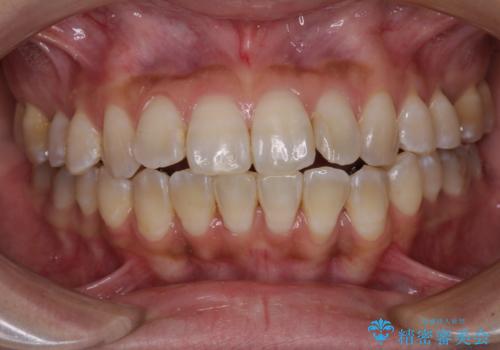

- 上下の前歯のでこぼこを気にして来院された患者様です。

職場の都合により、表側のワイヤー装置や着脱作業が頻繁なマウスピース矯正は困難とのことで、全く目立たない裏側矯正装置を用いて口元を整えることとしました。

途中転勤や出産があり、通院できない期間が長くありましたが、無事に歯列を整えることができました。